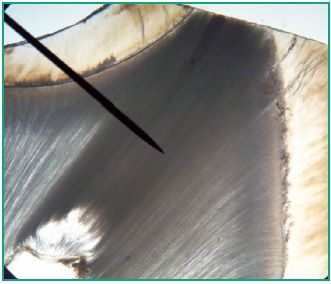

The histologic specimens obtained were classified according to the scale mentioned above, and analyzed using an optical microscope at different magnifications: 10x, 20x and 40x (Figs. 4-8).

Fig. 6. 20x microscope image of dentin in a tooth with grade II wear

The histologic specimens obtained were classified according to the scale mentioned above, and analyzed using an optical microscope at different magnifications: 10x, 20x and 40x (Figs. 4-8).

Fig. 6. 20x microscope image of dentin in a tooth with grade II wear

The enamel wear of teeth with Grade I wear was examined macroscopically on the occlusal/incisal surface, which showed microfractures that can be seen under white light. The areas of attrition appeared as polished and shiny surfaces when they only included enamel. The section of the enamel prisms of teeth with grade I wear was observed under the optical microscope at 20x magnification (Fig. 4). Dentin was translucent and yellowish, due to the deposit of peritubular dentin obliterating the dentinal tubules, all of which is consistent with sclerotic dentin (Fig. 5). In the cases where attrition only reached the enamel, the section of the adamantine prisms observed was consistent with tissue that does not respond to any stimuli. The presence of reactive or defensive dentin was observed. The microscopic examination of the teeth with grade II wear, according to the modified scale, showed discontinuities on the enamel on the areas closest to the outer tooth surface, and the peripheral areas of the dentin showed wear in small spots (Fig. 6). The teeth with grade III wear showed exposed dentin, and a central opaque yellow concavity surrounded by irregularly worn enamel which was visible to the naked eye. Sclerotic dentin was observed in the periphery, and dead or devitalized tract dentin was observed in the center of the teeth under the optical microscope at a 20x magnification (Fig. 7). At a higher magnification (40x), it can be seen that the dentinal tubules were empty, covered in germs and organic residue from the mouth (Fig. 8). They seemed dark due to the contamination with the wear technique material and the balm used to prepare the histologic specimen. Dead tract dentin was visible with 20x and 40x magnification due to the fact that the wear took place in a short period of time and there was no time for the odontoblasts to retract. However, some teeth showed both types of dentin.